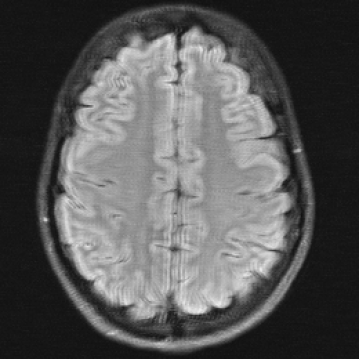

The reconstructions in Figure 5 were obtained by the application of E2E-VarNet, Figure 5 (b)(c)(e)(f), and XPDNet, Figure 5 (a)(d), to accelerated data with random masks (acceleration factor between 1 to 5) in the frequency domain.

Figure 5: Reconstruction outputs of accelerated FLAIR MRI data from the algorithms Xpdnet(a)(d) and E2varnet (b)(c)(e)(f). The bottom images (d)-(f) are judged by PSNR/SSIM/LPIPS as better reconstructions than the respective image above them (a)-(c), although visually they clearly have worse quality.

We can see in Figure 5 that the visual quality of the obtained images does not correspond to the numbers provided by PSNR/SSIM/LPIPS. This is not surprising as some challenges with SSIM as a performance metric have already been discussed in the official results paper of the challenge (citep \@BBN(Muckley et al., 2021a)) and small artefacts/wrong lesions have been shown. Here, we complement with examples where the visual results clearly ask for a different judgement even in a non local manner. In particular, the bottom images in Figure 5 show stronger artefacts and loss of information in comparison to the images on top. In addition, the degraded images (e) (f) do hold quite higher numbers in comparison to (a) which is nearly noise-free.